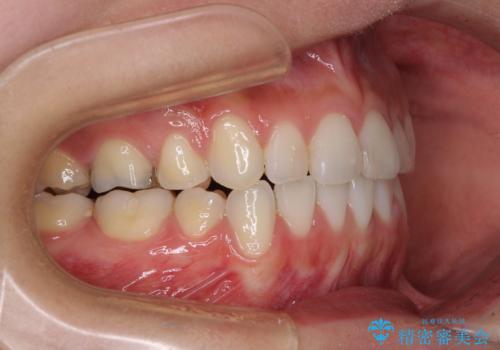

- 上下の八重歯を気にして来院された患者様です。

上下ともに八重歯の後ろの歯を1歯ずつ抜歯し、補助装置(リンガルアーチ)を用いて八重歯の位置を改善し、その後インビザラインにより矯正治療を行うこととしました。

途中海外留学をされたため、治療期間は長くなりましたが、事前に補助装置やワイヤー装置を併用したことで、きれいな歯列に仕上げることができました。